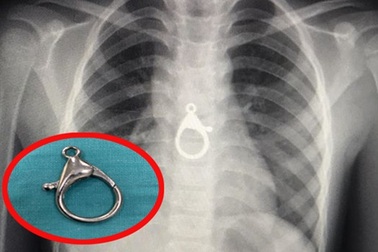

Ngậm móc khóa trong miệng, cậu bé gặp họa khi chơi cùng emĐang ngậm chiếc móc khóa trong miệng chạy đùa với em, cậu bé 5 tuổi bất ngờ ho sặc. Hơn 2 tháng sau, chiếc móc khóa kim loại đã gây xẹp phổi, đe dọa tính mạng bệnh nhi.

Quảng Nam: Nuốt phải móc khóa, bé 6 tuổi tuổi nhập viện cấp cứuKhoa Tai Mũi Họng Bệnh viện Đa khoa tỉnh Quảng Nam cho biết, đơn vị vừa gắp thành công 1 móc khóa xe ở vùng ngực cháu trai 6 tuổi ra ngoài an toàn.